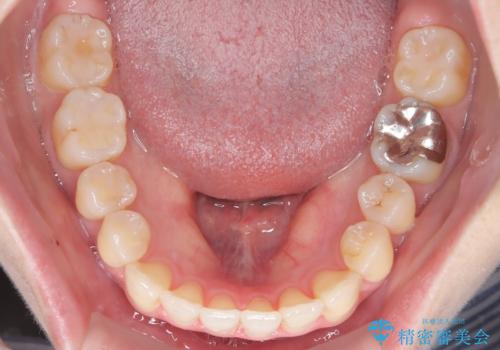

- 前歯のガタガタを主訴に来院された患者様です。

前歯の傾きも少し内側に入るように計画をたて、インビザラインにて治療を行いました。

このぐらいのガタガタであれば、インビザラインで簡単に治すことができます。